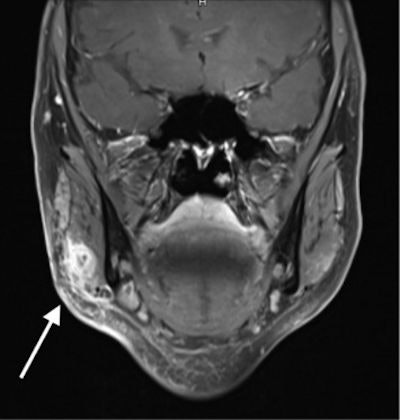

The patient had a hardened, tender swelling near the right angle of the jaw (white arrow). All images courtesy of Becker et al. Licensed under CC BY-NC 4.0.Hyaluronic acid fillers are temporary dermal fillers that reduce the appearance of fine lines and wrinkles and add volume to the face and lips. Though results can be seen immediately, they are only temporary. Other fillers are available, but hyaluronic acid fillers are used most often because they have low antigenic potential and are known to cause fewer adverse effects.

Coronal MR image (above) shows a lesion in the right masseter muscle approximately at the level of the jaw angle (white arrow), within and overlying the lateral masseter margin. Axial MR image (below) shows inflammation involvement of the surrounding adipose tissue and the right ventrocaudal parotid tip (white arrow).The findings were compatible with an inflammatory mass, and it was punctured and aspirated. No blood or pus emerged, which was appropriate for an accumulation of hyaluronic acid filler. Intravenous antibiotics were continued until the woman's symptoms regressed. If her symptoms had persisted with additional treatment, surgical resection would have been a final option, according to the authors.